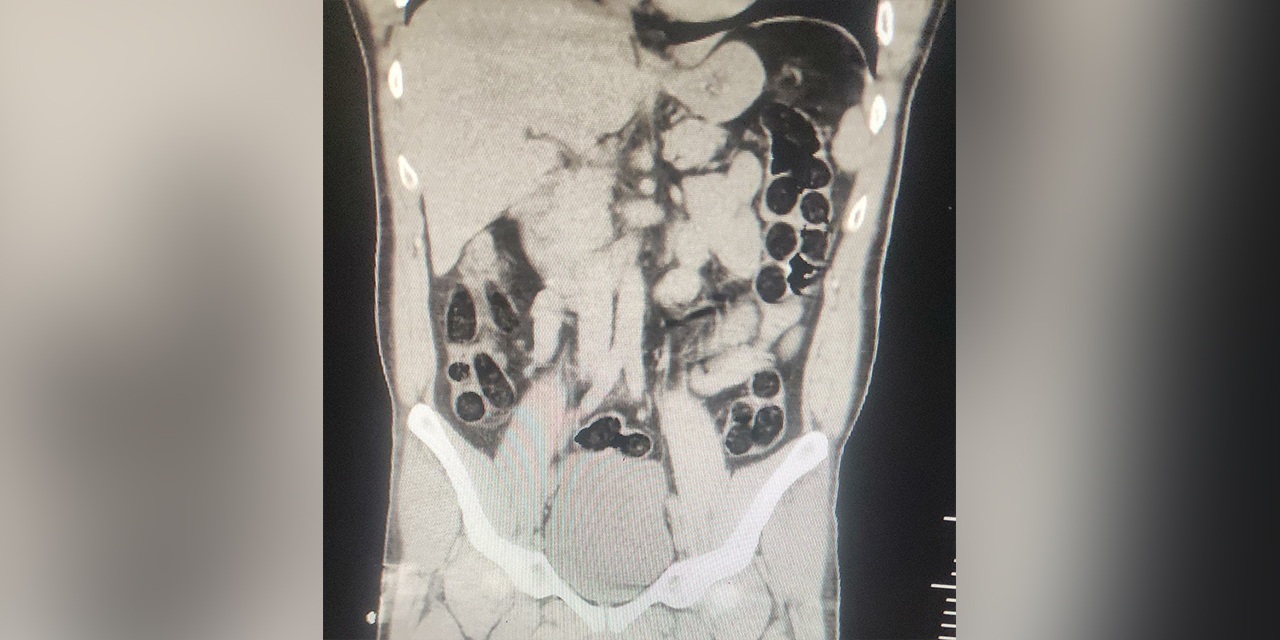

Batman'da İran uyruklu olduğu belirlenen bir kişinin midesinden 76 paket halinde 714 gram eroin çıktı.

Operasyonda; otobüs ile seyahat eden 2 İran uyruklu şahsın yapılan kontrollerinde ve iç beden muayenesi sonucunda, şahıslardan birinin midesinde 76 paket halinde, 714 gram eroin maddesi ele geçirildiği belirtildi.